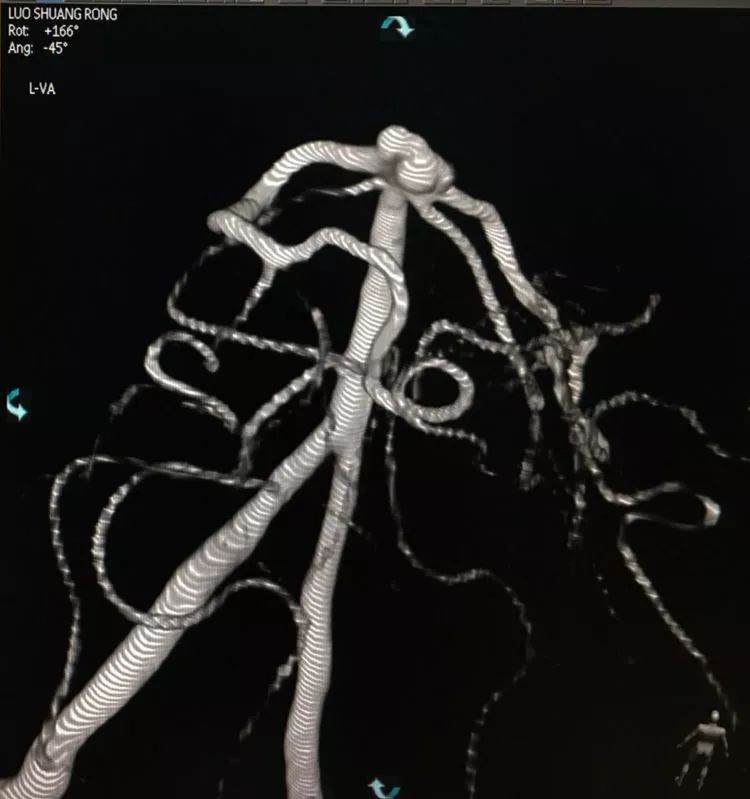

左椎动脉造影三维重建和测量

回头再观察左椎动脉造影的三维成像,发现瘤腔确实有向后方突出的分叶,明确弹簧圈团后部的空虚处仍是瘤腔的一部分